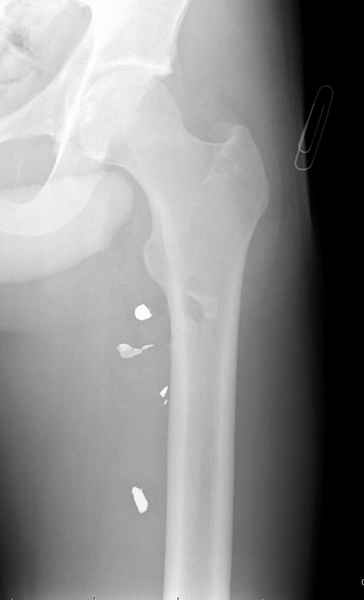

Больной с огнестрельным переломом бедра с вовлечением около 15% медиального кортекса, входное отверстие около 1 см в диаметре; стабильный, без сосудистых и неврологических признаков.

Учитывая, что больной получил травму не во время визита в церковь, и он является одним из представителем 40 миллионного “outstanding itizen”, без медицинской страховки, без работы в свои 39 лет, и без надлежающей ортопедической дисциплины у которого отсутсвует страх стрессового перелома, было рекомендовано оперативное лечение: профилактическое антеградное интрамедуллярное штифтование.

Методика штифтования при отсутствии большой зоны перелома как при онкологических профилактических штифтованиях, расверливание интрамедуллярного канала проводим с предварительным наложением дополнительного дренажного отверстия в дистальном отделе бедра (в данном случаи в канале оставили 6.5 мм канюлированный шуруп), иначе при создании давления в канале во время сверления имеется опасность эмболизации легочной артерии тромбом.